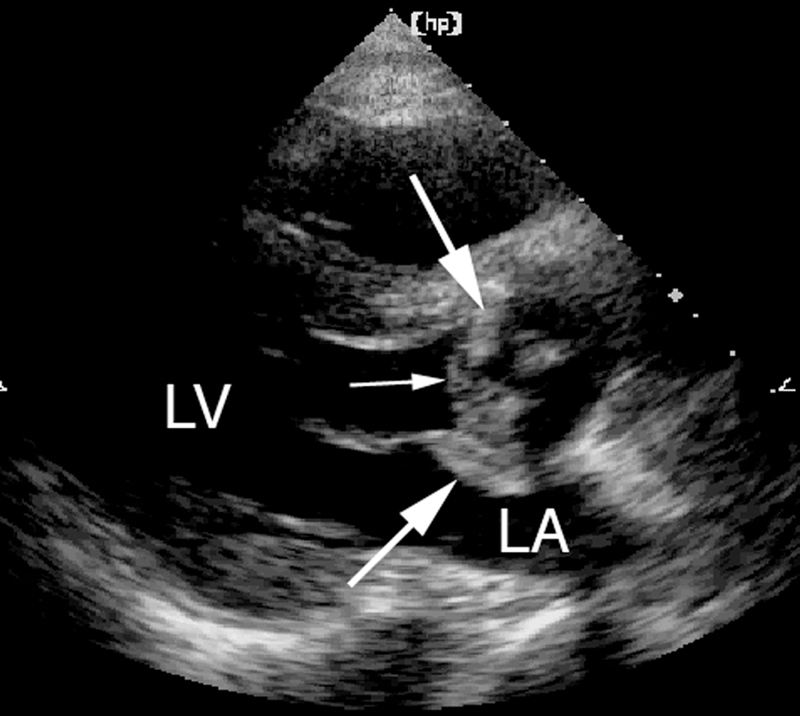

فحوصات تشخيصية لبعض امراض القلب والشرايين التاجية